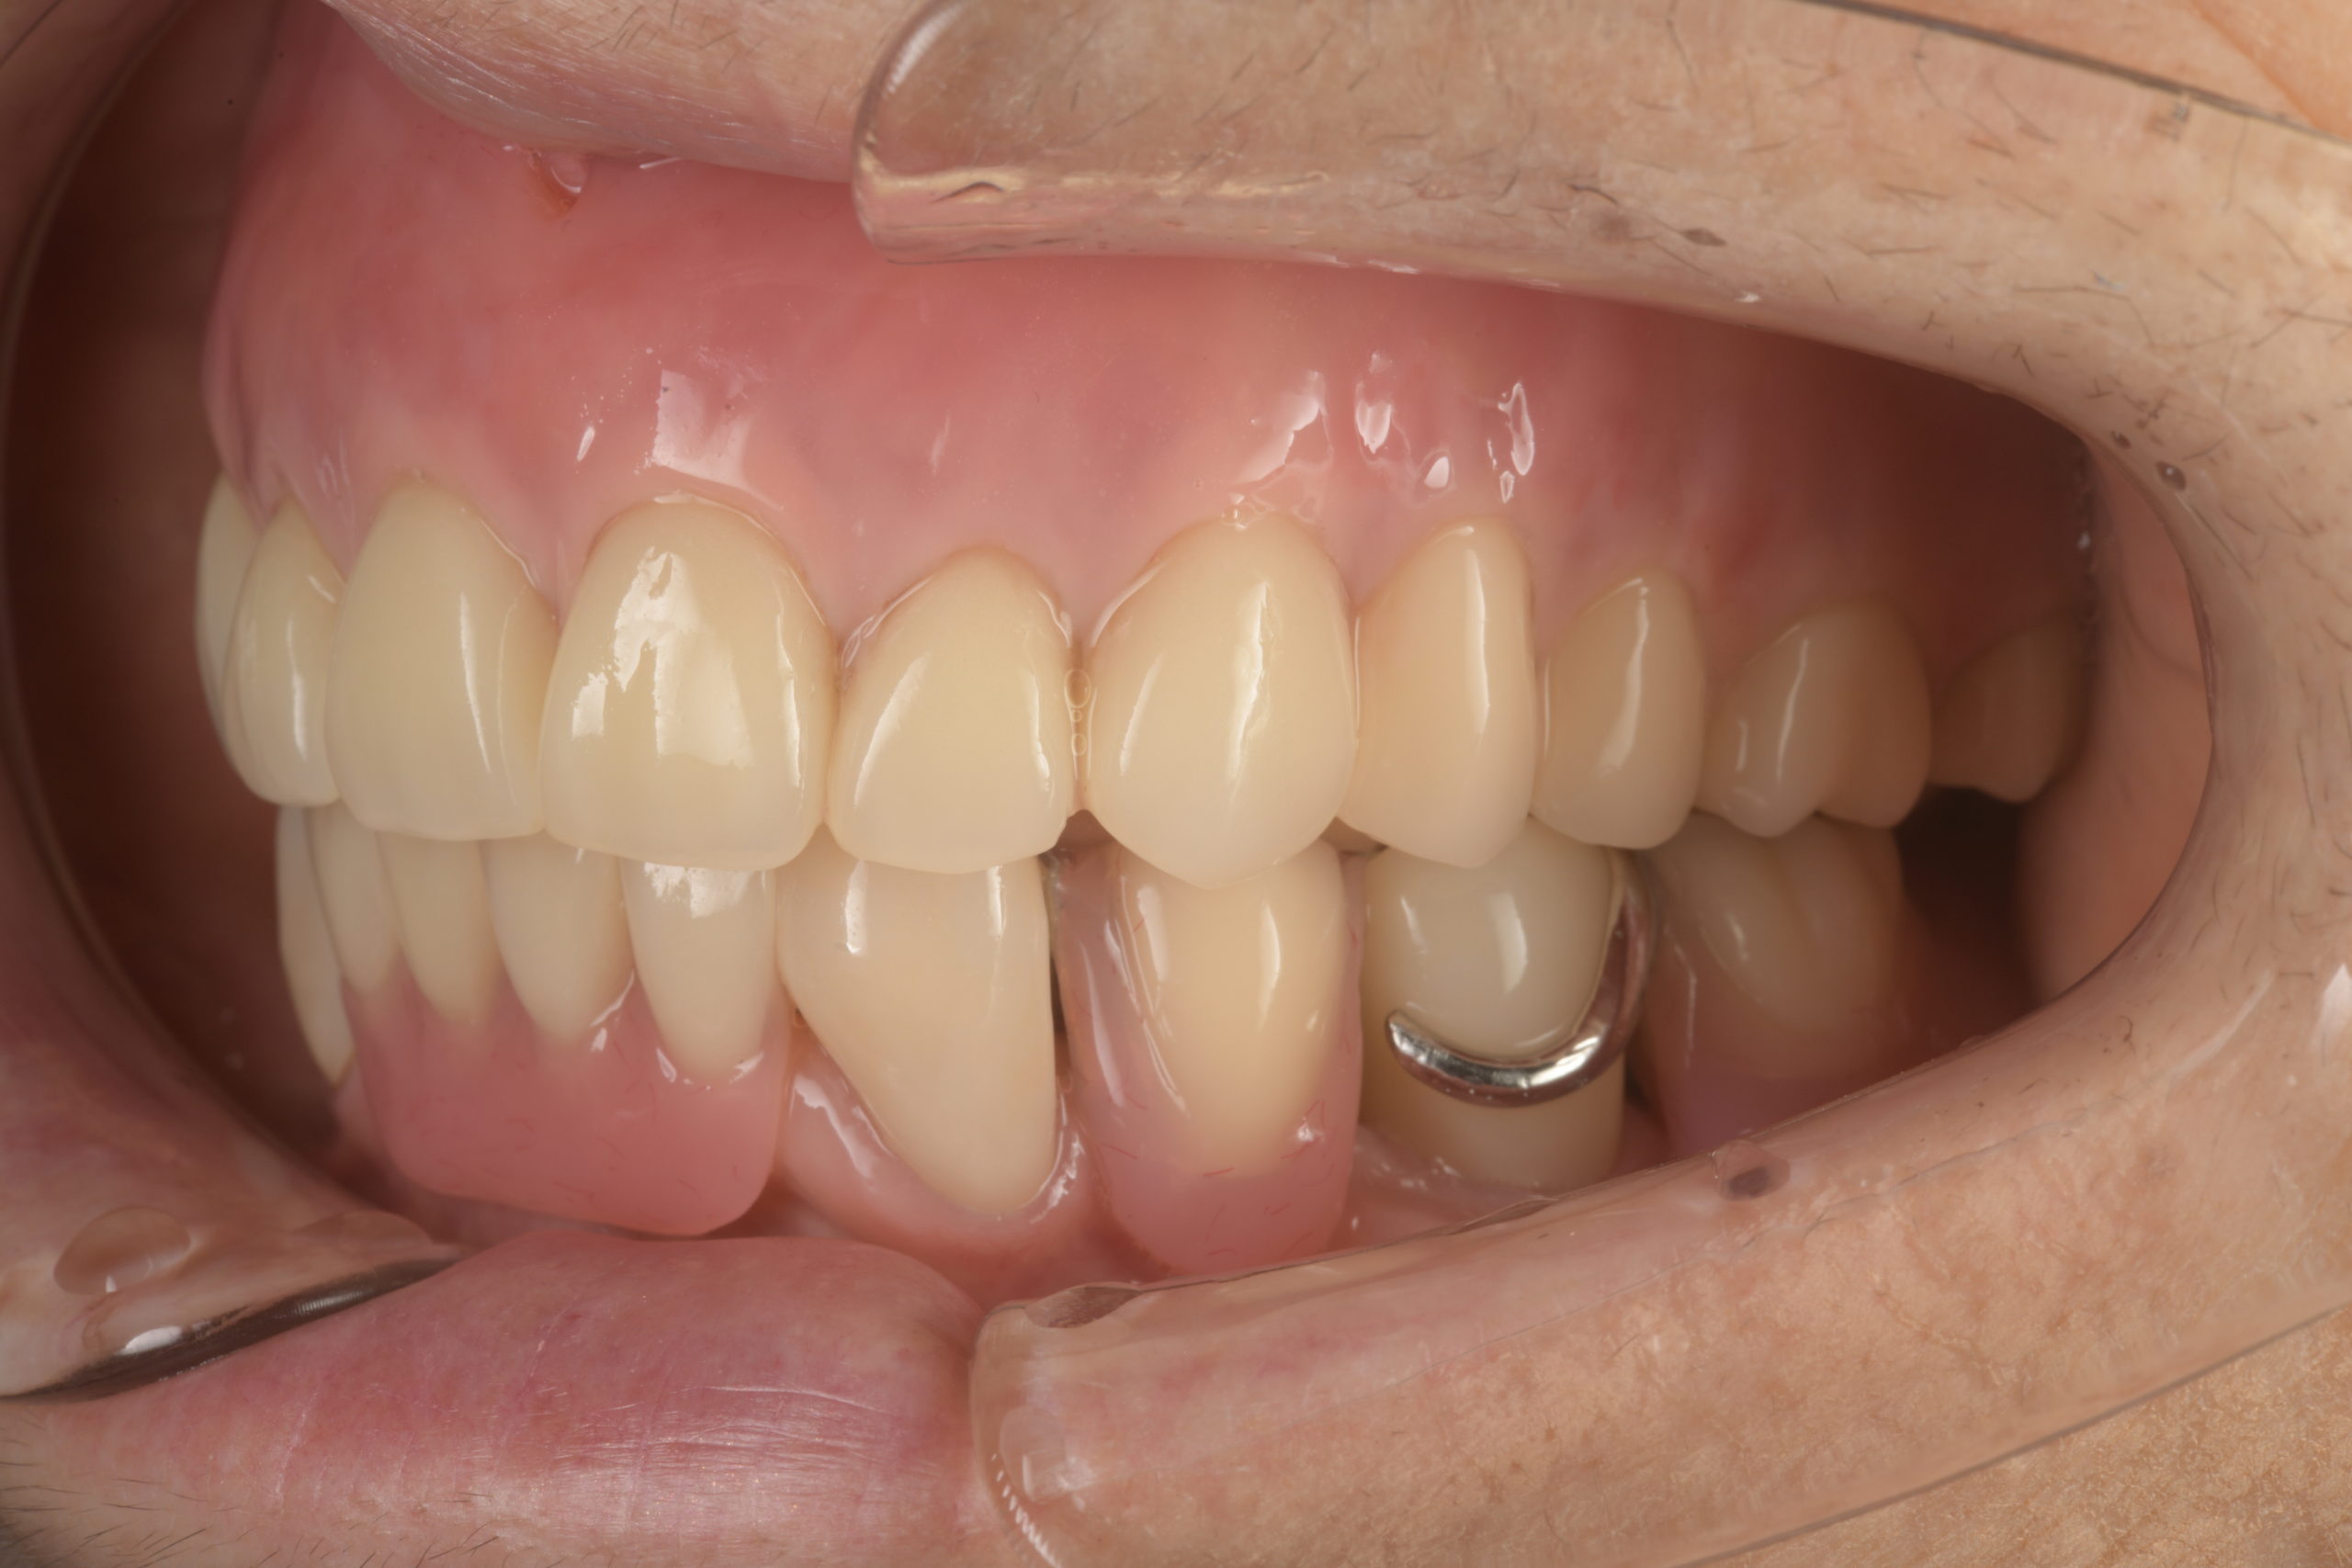

患者様は70代女性。左下の奥歯の痛みと義歯の作り直しを希望され来院されました。義歯の作り直しについては、できるだけ違和感のないもので、かつ見た目も綺麗な口元にしたいとのご要望がございました。 左下の奥歯は重度の歯周病のため抜歯を行い、その後残りの歯をセラミッククラウンにて補綴し、上下の金属床義歯を作製致しました。 治療後の経過は良好で、患者様より「上の入れ歯も下の入れ歯もピタッとしていて非常に快適です。上の入れ歯は以前のように食事中落ちてくることもなく非常に食べやすいです。見た目も綺麗な口元になり非常に満足しています。ありがとうございました。」とのお言葉をいただきました。 当院ではこのような機能的、審美的に良好な精密義歯治療に力を入れております。お気軽にご相談ください。 |

治療後